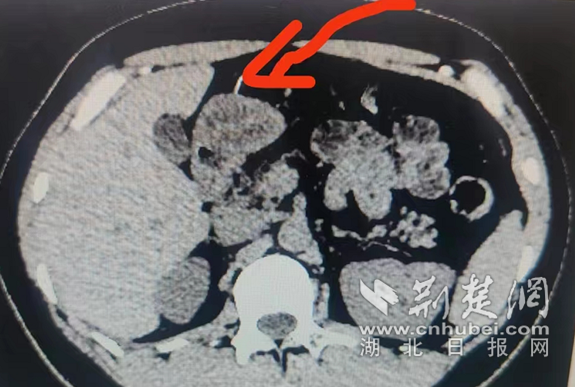

鱼刺沿着食道“顺流而下”进入胃里并戳穿胃壁 通讯员供图

荆楚网(湖北日报网)讯(通讯员李晗 张翼飞)男子吃饭太快,不慎将一根1.8公分的鱼刺整根吞下,鱼刺沿着食道“顺流而下”进入胃里并戳穿胃壁。一旦进入腹腔,就会成为一颗伤害胃肠肝胆胰等内脏器官的不定时炸弹。医生通过腹腔镜微创手术,将鱼刺完整取出。

40岁的林先生一周前在吃午饭时,由于赶时间不慎将一根1.8公分的鱼刺整根吞下。当时他觉得喉咙没有异物感,但两个小时后觉得隐隐腹痛,家人带他到武汉大学中南医院检查,发现一根1.8公分的鱼刺戳穿了胃壁,随时可能成为在腹腔里游走并伤害肝、肾等内脏器官的不定时炸弹,必须尽早取出。由于鱼刺已经戳穿胃壁,无法进行常规的胃镜取刺,中南医院胃肠外科程伏林主任医师、张春晓博士立即为林先生进行腹腔镜微创手术,通过在林先生的肚子上打3个小孔,顺利将被大网膜包裹的鱼刺完整取出。返回病房后,给予抗感染、补液等对症支持治疗。术后第三天,林先生康复出院。11月1日复查,他的伤口已经恢复并顺利拆线。

程伏林推测,林先生吞下鱼刺后,鱼刺顺着食道一路滑入胃中,尖又硬的鱼刺戳穿了胃壁,幸亏被大网膜包裹住,避免了鱼刺进入腹腔带来更大的伤害。